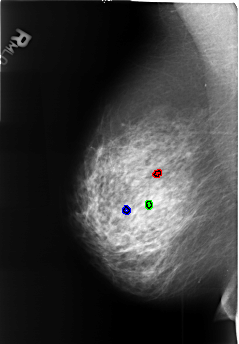

B_3449_1.RIGHT_MLO

FILE: B_3449_1.RIGHT_MLO.OVERLAY

TOTAL_ABNORMALITIES 3

ABNORMALITY 1

LESION_TYPE CALCIFICATION TYPE LUCENT_CENTERED DISTRIBUTION N/A

ASSESSMENT 2

SUBTLETY 3

PATHOLOGY BENIGN_WITHOUT_CALLBACK

TOTAL_OUTLINES 1

BOUNDARY

ABNORMALITY 2

ABNORMALITY 3